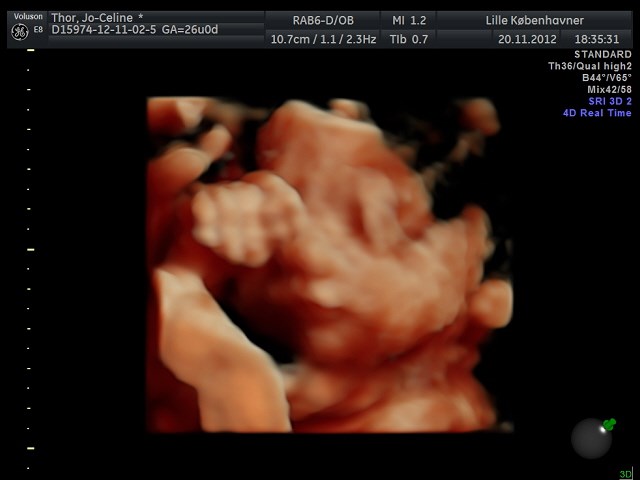

Søger man på Google kommer der kun 3D-billeder.

Så jeg vil høre om nogen herinde har et billede eller to fra uge 28 de vil vise? Og hvor lang var jeres baby, og fik I vægt at vide?